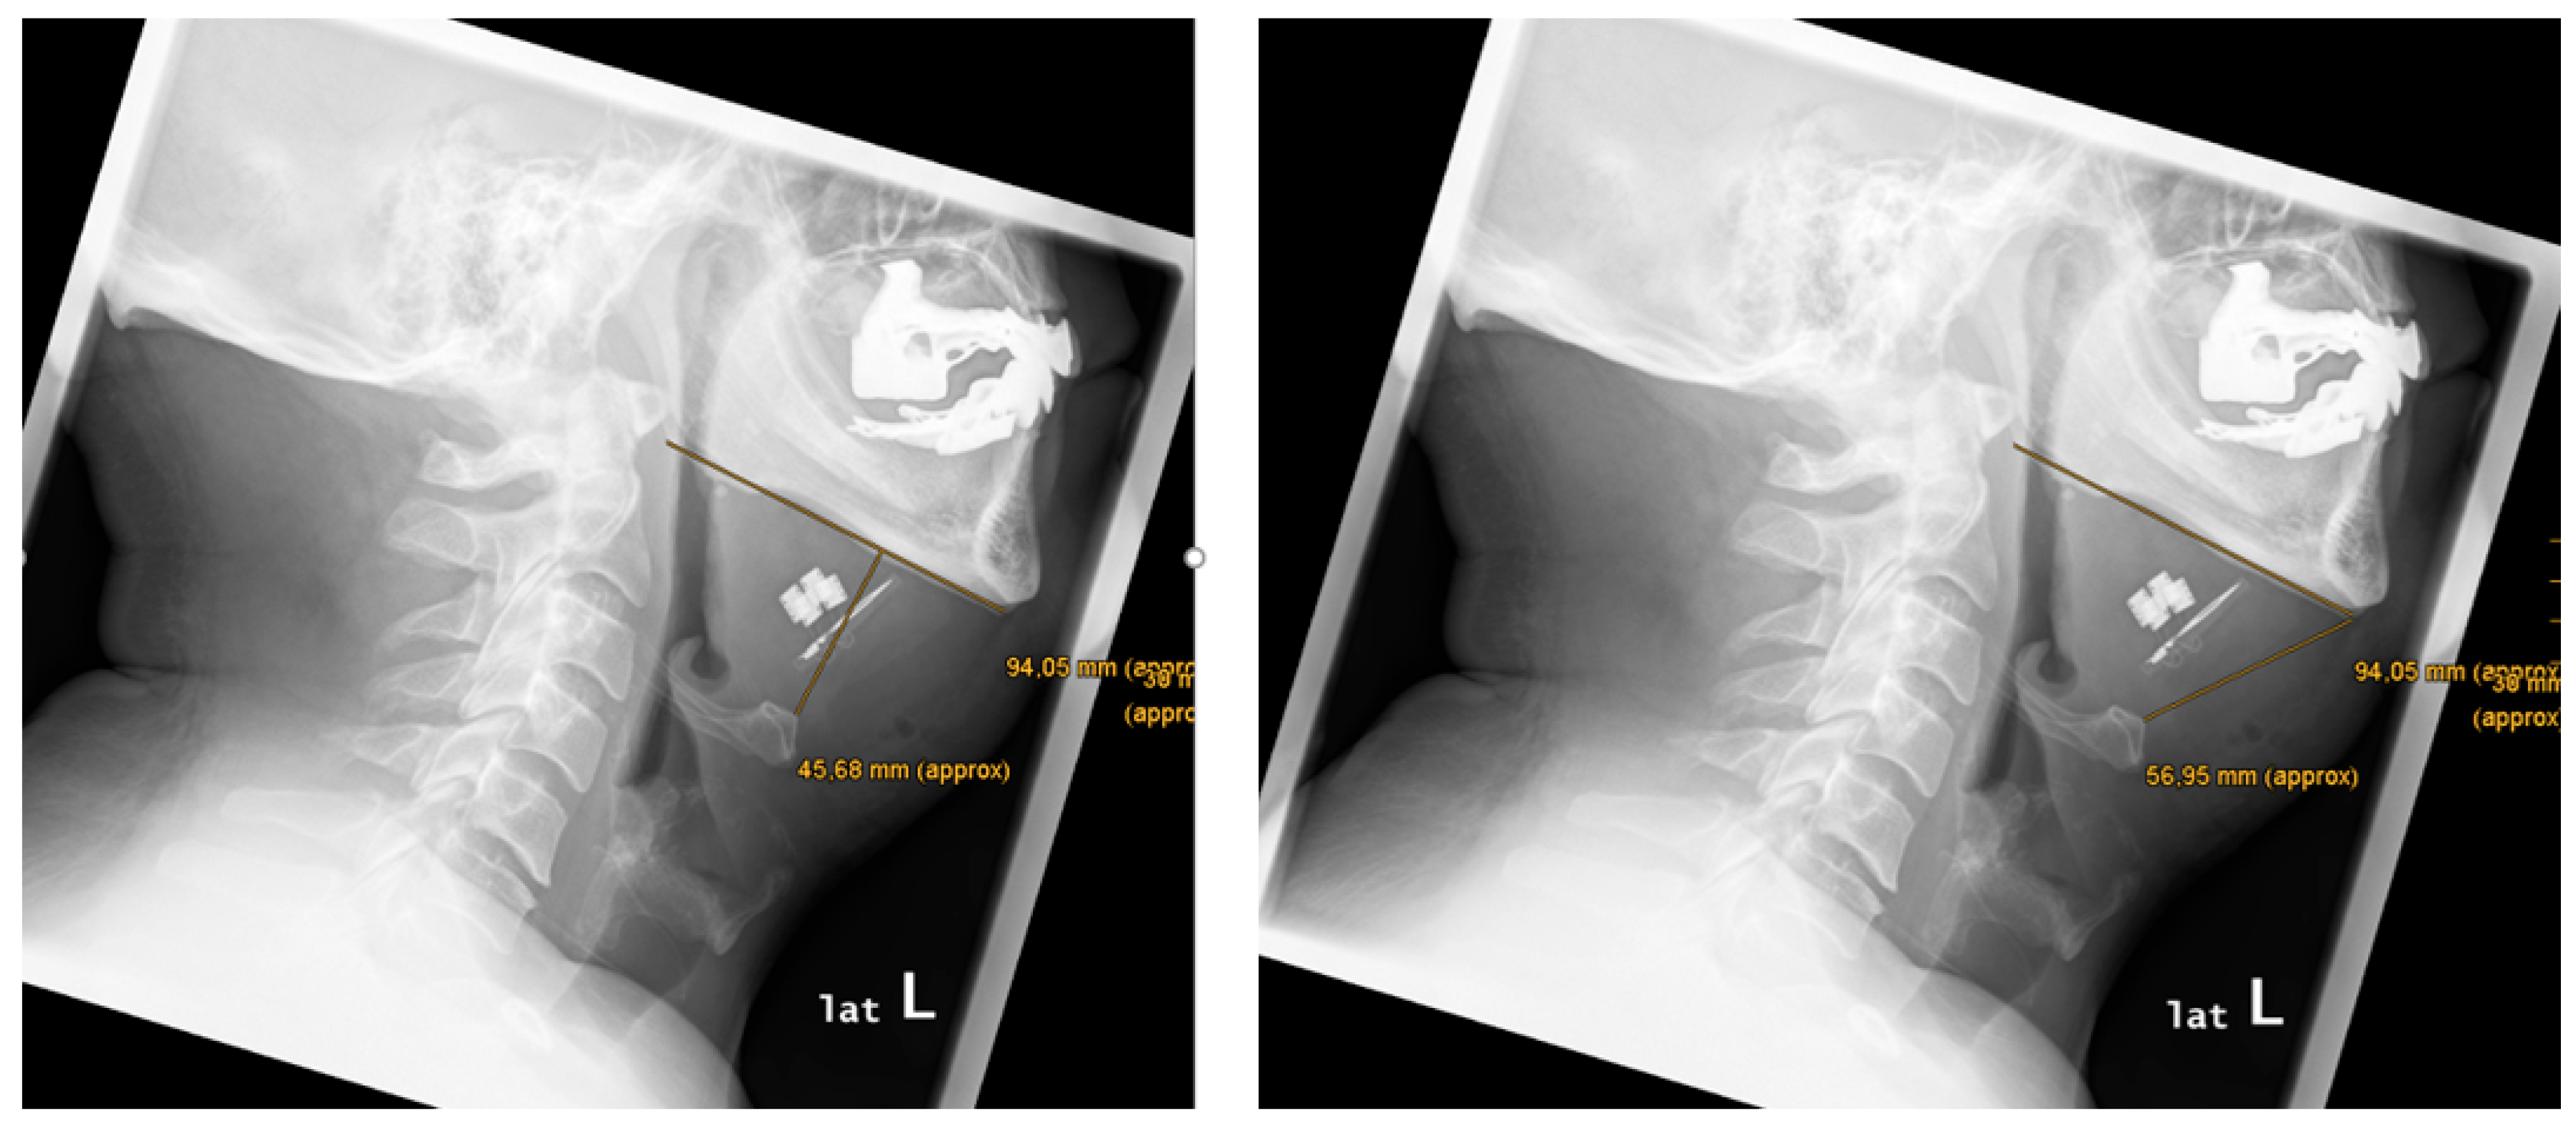

| 2 | 47 | 30 | yes | yes | yes | strong | no | yes | 94,1 | 45,7 | 57,0 | 19,0 | 18,7 | 19,3 | -0,6 | symmetry | 70,4 | proximal | proximal |